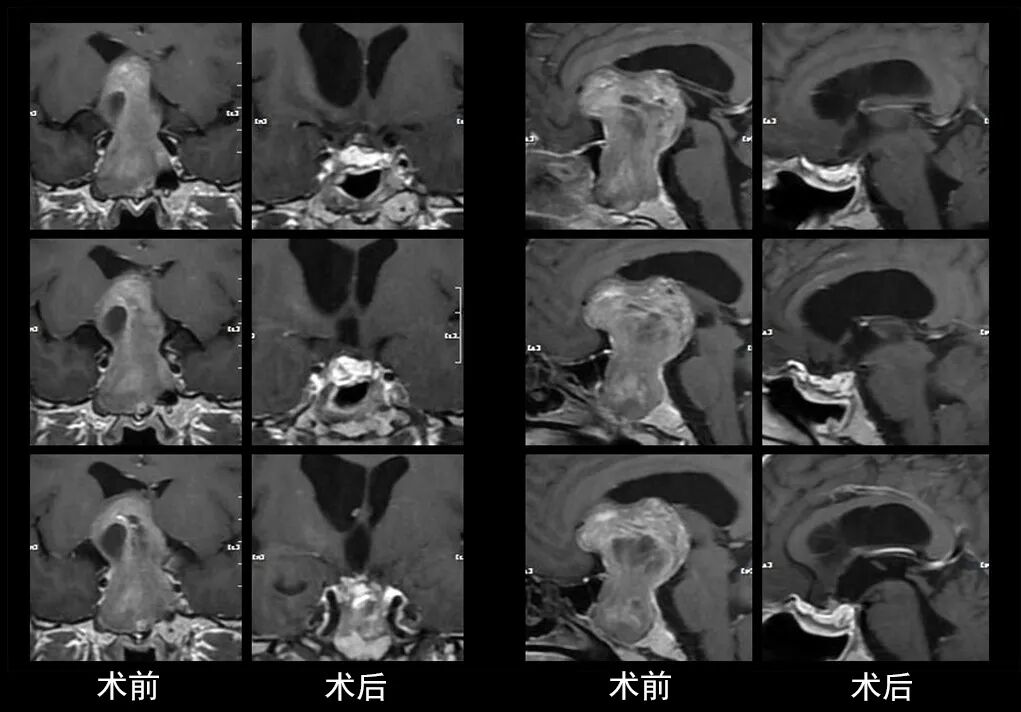

本研究中采用联合手术策略的代表性病例展示:

左右滑动查看更多

图片

case 5

case 6